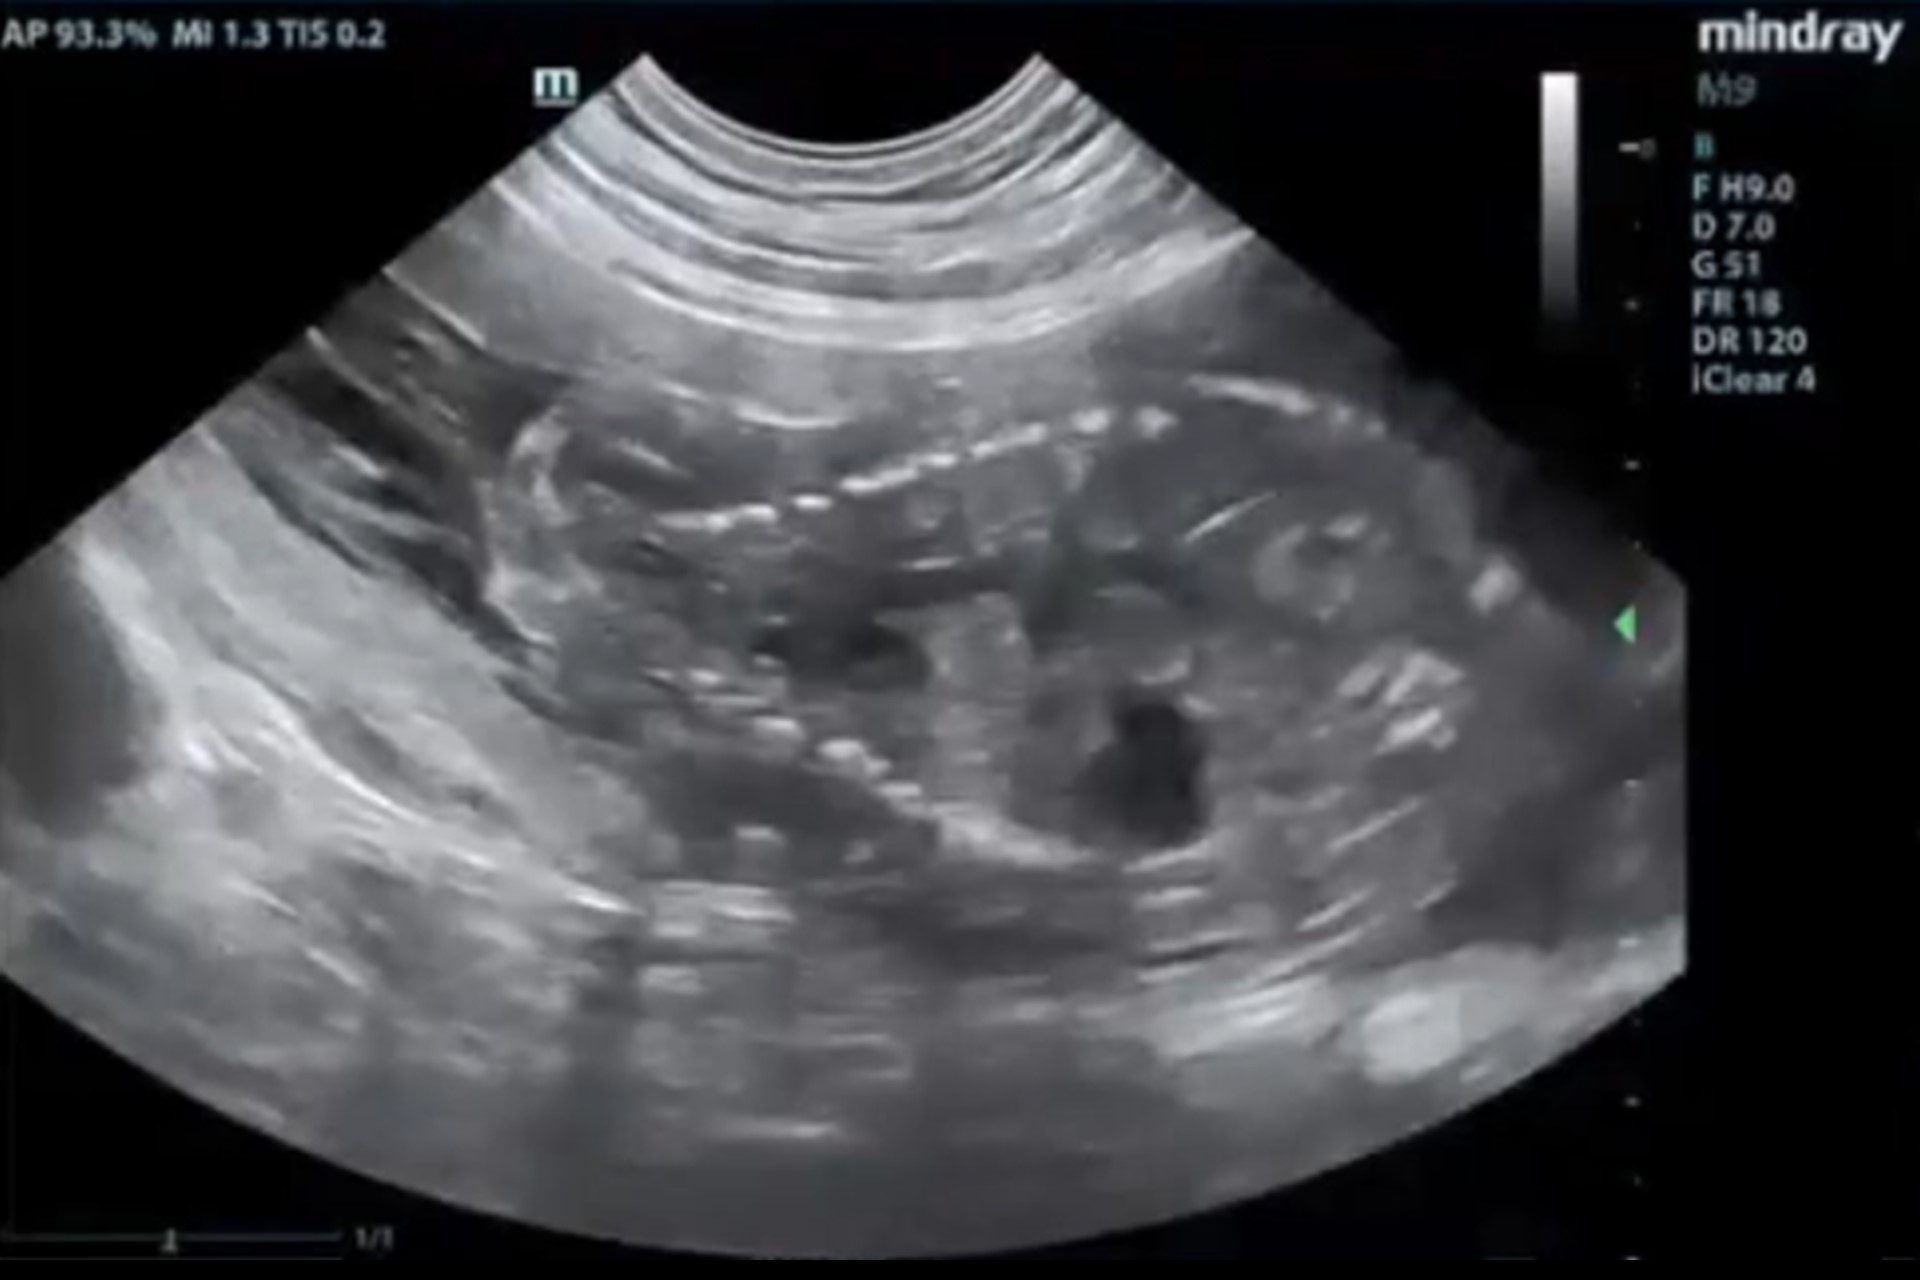

Ecografía abdominal

Evaluación detallada de todos los órganos abdominales. Permite detectar masas, cuerpos extraños, procesos inflamatorios, alteraciones urinarias o reproductivas, así como enfermedades hepatobiliares o gastrointestinales.